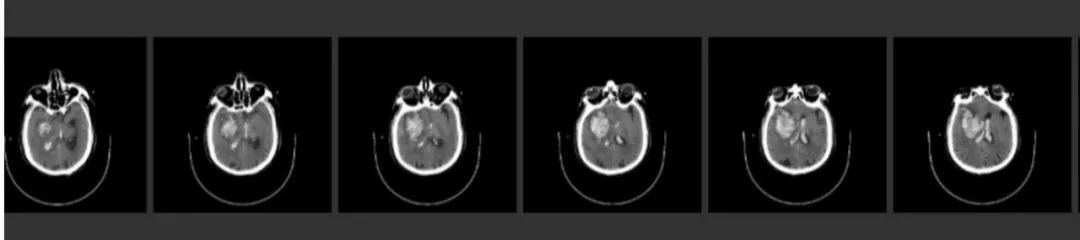

术前CT

ASPECTS评分 8分

术后即刻CT

术后24h CT

术前NIHSS评分16分

术后24hNIHSS评分 2分

术后48hNIHSS评分

术后第3天,患者突然意识丧失,呼叫无反应,刺激右侧肢体无反应,左侧可见回缩,紧急头颅CT提示左侧半球大量脑出血并破入脑室,很快左侧瞳孔散大,深昏迷,家属拒绝行开颅血肿清除术,自动出院。

术后3天CT: